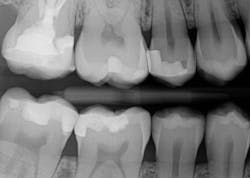

A 27-year-old patient was referred to me due to discomfort associated with dentinal hypersensitivity secondary to erosion on his posterior teeth (figure 1 above: Initial presentation. Note the exposed dentin due to erosion). His former dentist suggested crown lengthening due to inadequate space for full-coverage crowns.

After a thorough evaluation of his clinical presentation, radiographs, and intraoral scan, it was evident that the discomfort was due to exposed dentin. The intraoral scan confirmed there was adequate interocclusal space to restore the eroded tooth structure with a minimally invasive approach (figure 2). All options were reviewed with the patient, and it was mutually agreed upon to address his chief complaint in this manner. Proper isolation is critical for reliable bonding.

Caries lesions were removed and air abrasion was employed to remove impurities on the unprepared tooth surfaces and create increased surface area for bonding. Preparation of the class II carious lesions revealed demineralization on the adjacent tooth structure (figure 3). When lesions such as these are discovered, dentists are often at a crossroads whether to intervene or monitor the area for progression. It is my experience that these early caries lesions can be predictably arrested with resin infiltration (figure 4), and that no intervention usually results in the progression of caries.

In this case, lateral access was achieved by the preparation of the adjacent teeth as part of the proposed treatment plan. Early caries lesions that are noted on radiographs that are not accessible in cases such as this one can be accessed by placing an orthodontic spacer. This patient was restored with direct composite bonding (figure 5) and these restorations have proven to have a favorable long-term outcome (figure 6).